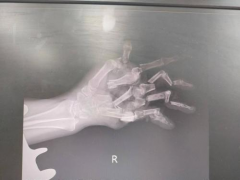

女子五根手指被“绞碎”医院消防合力救援

女子五根手指被绞碎医院消防合力救援 自从有了绞肉机,剁肉不用再剁到手酸,方便快捷,但在使用这些机器...